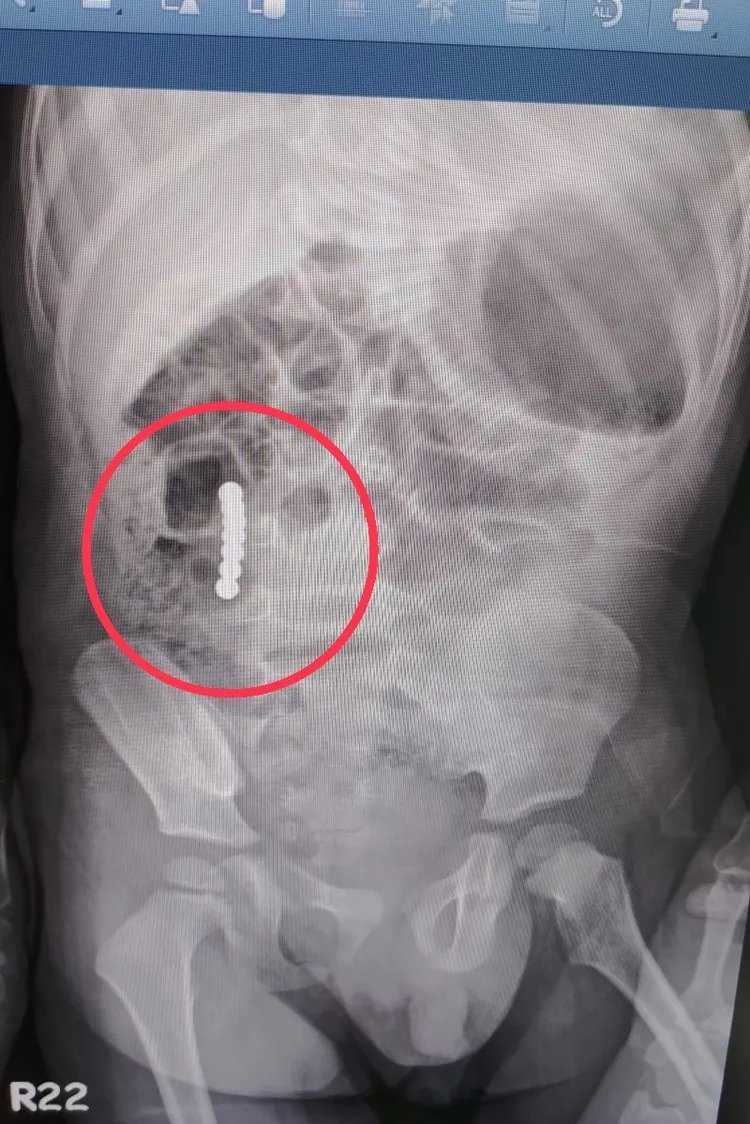

蔡煥文說明,該2歲男童到院時已觀察到腹膜炎症狀,幸好沒有休克跡象。X光檢查顯示7顆巴克球連成一直線,缺少經驗的話可能誤以為在同一腸段,就以一般異物吞入處理原則處置,慢慢等待其自行排出。然而,其中3顆在小腸內、4顆位在大腸,每顆互相吸引造成腸扭轉而阻塞,且吸力過強才進一步導致腸穿孔。